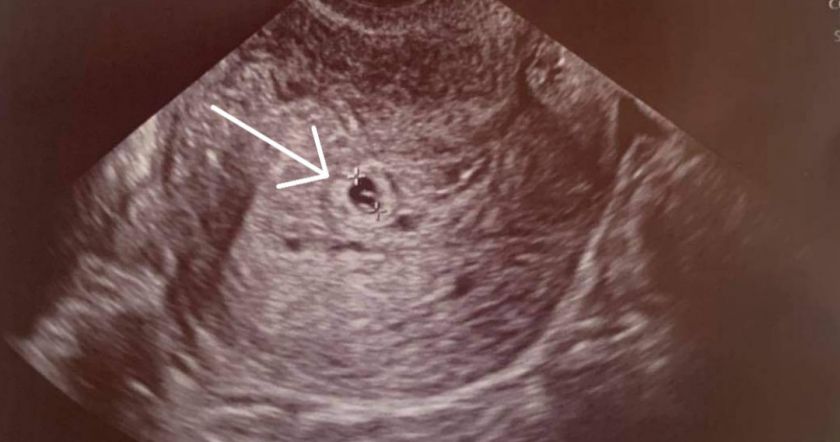

44 օրյա պատերազմում եղբորը կորցրած պացիենտը հղիացել է երկար տարիների անպտղությունից հետո։

Աննկարագրելի հուզիչ էր մոնիտորին տեսնել այս փոքրիկ, բայց մի ամբողջ ընտանիքի նոր կյանքի լույս տվող կետը»։